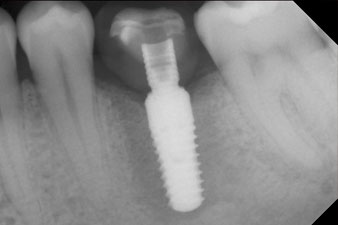

The implant was uncovered two months later and a gingiva former was screwed in (no picture).

After healing of the soft tissue, the implant stability was measured again before delivery of the prosthetic restoration.

Both values were virtually unchanged and were between the medium and the high range – where the lower value is always used as the reference value that determines the treatment.

Therefore, successful osseointegration and adequate biological stability could be recorded, which enabled an impression to be taken in the same session.

The final pictures show the screw-retained monolithic composite crown in place and the x-ray check (Fig. 9 and 10) (6).